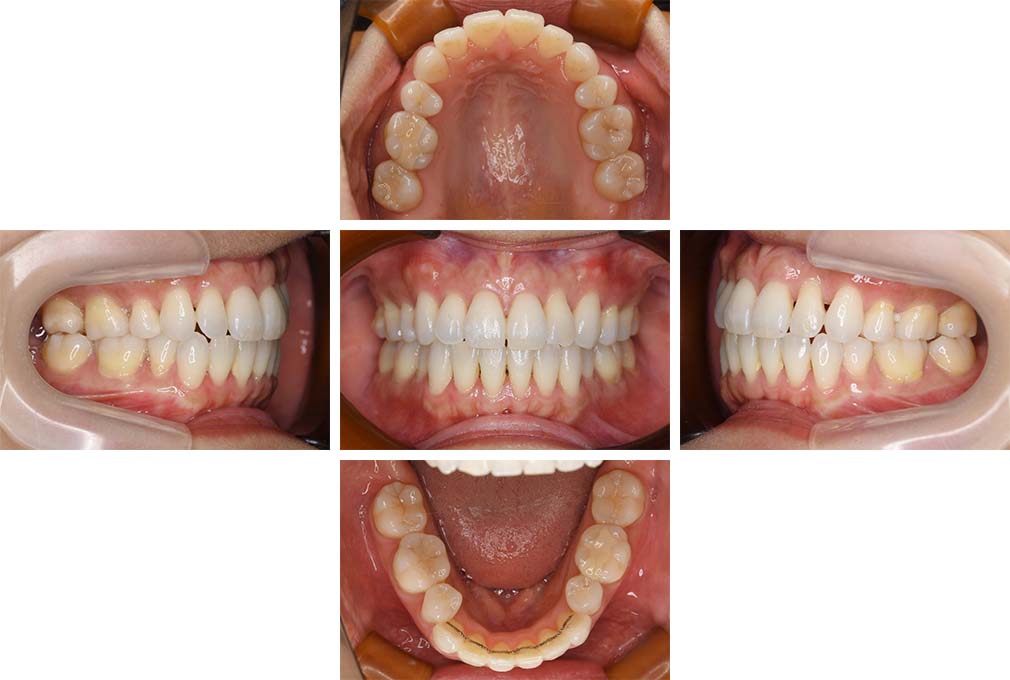

CASE:02

下顎前歯部叢生、小臼歯4歯先天欠損

初診時年齢 14歳3か月

性別 女性

治療費の目安 70万円(治療開始時)

上顎左右側小臼歯3歯、下顎左側第二小臼歯の先天欠損と下顎前歯の叢生を主訴として近隣一般歯科から紹介来院した。

上顎左側第一、第二小臼歯、右側第一小臼歯、下顎左側第二小臼歯が先天欠損であったが、左上第二乳臼歯の根の吸収がほぼ無いことから、これを残すこととして、下顎左側乳臼歯と、右側第二小臼歯を抜歯していただきマルチブラケット装置を使用して動的治療を行った。矯正用ゴムなどの協力状態も良く2年0カ月(調整来院19回)で装置を撤去し保定へ移行した。動的治療終了13年2カ月での来院時には下顎左右側智歯が萌出していたが、垂直的に萌出していたため抜歯は行っていない。

治療前

14歳3か月

治療後

動的治療期間2年0カ月

16歳7か月

13年経過

動的治療終了後13年2カ月

30歳0か月